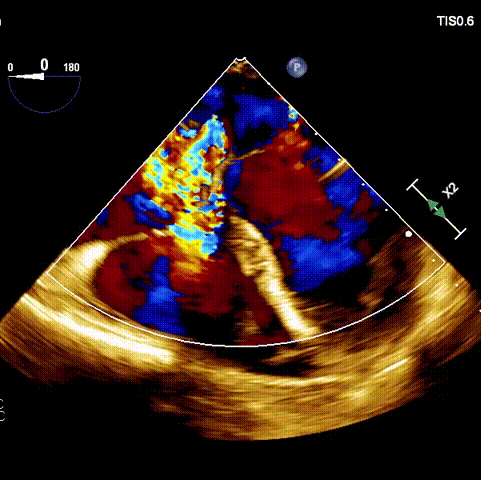

術(shù)前超聲

接受手術(shù)的為一名80歲男性,因“心悸2年,氣喘伴下肢水腫半年”入院。超聲心動提示“極重度三尖瓣反流,右房及右室明顯擴(kuò)大,右心收縮功能輕度減低,左心收縮功能正常,肺動脈壓力正常”?;颊咄瑫r合并有“持續(xù)性房顫”及“慢性心力衰竭”,病史持續(xù)2年,規(guī)律口服抗凝及強(qiáng)心、利尿治療治療效果不佳,癥狀持續(xù)。經(jīng)廈心心臟團(tuán)隊(duì)評估后,認(rèn)為患者三尖瓣極重度反流并伴有心衰表現(xiàn),長期內(nèi)科藥物治療效果不佳,且患者高齡、外科手術(shù)風(fēng)險(xiǎn)高,因此決定采用微創(chuàng)經(jīng)頸靜脈LuX-Valve Plus三尖瓣置換系統(tǒng)為患者治療。